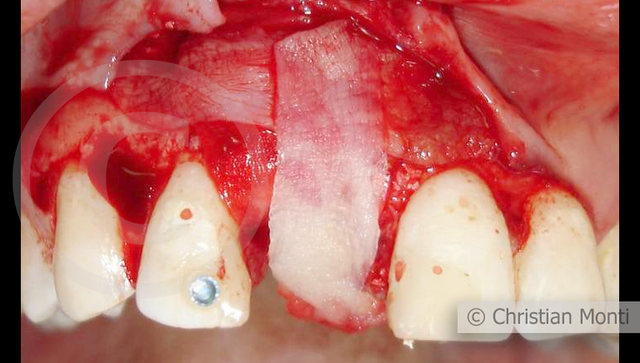

EDENTULIA SINGOLA

Impianto in sostituzione di un incisivo superiore